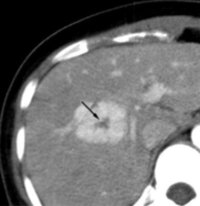

肝臓がんを見極めろ 造影ctでわかる肝血管腫と肝細胞がんの違い 心臓弁膜症 手術 みどり病院 神戸市西区

肝臓を占拠する パート1 できもの 悪くないもの 腹部超音波検査 Vol 3 心臓弁膜症 手術 みどり病院 神戸市西区